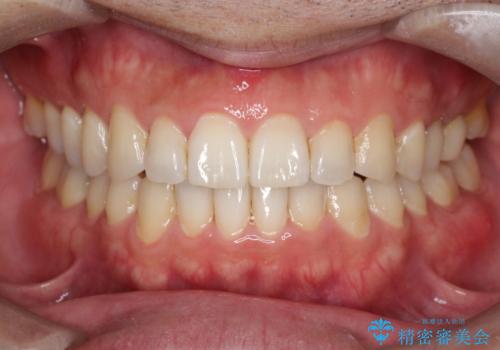

- 前歯の隙間を主訴に来院されました。

マウスピース矯正にて、隙間を綺麗に閉じることができ満足していただきました。

前歯の隙間を閉じる際は、前歯部の突き上げが懸念されるため、適切な治療計画が必要となります。